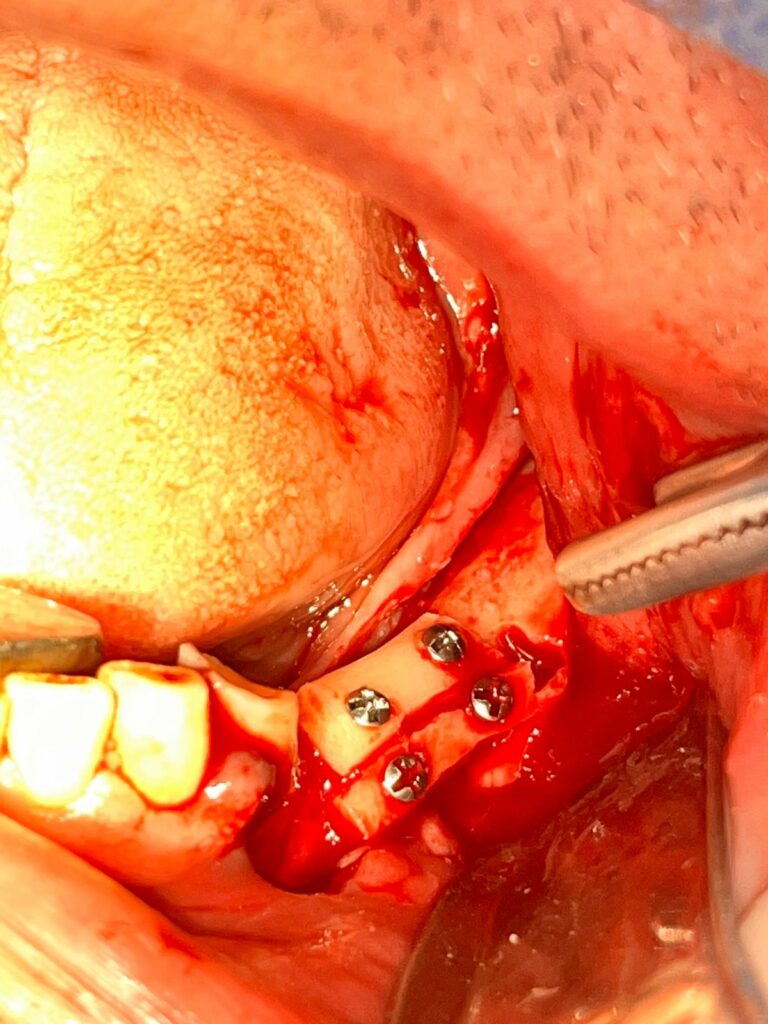

100% Chiruriga su pazienti

5. Prelievi ossei e Tecniche Ricostruttive

100% Chiruriga su pazienti

3 CASI ZYGOMA GARANTITI

1. Impianti Zigomatici

100% Chiruriga su pazienti

SII TU IL PRIMO OPERATORE, SEMPRE! DALL’INIZIO ALLA FINE. IL TUO ASSISTENTE SARA’ UN TUTOR DEDICATO CHE TI SEGUIRA E GUIDERA’ PASSO DOPO PASSO NELLA RISOLUZIONE DEL CASO CHIRURGICO!